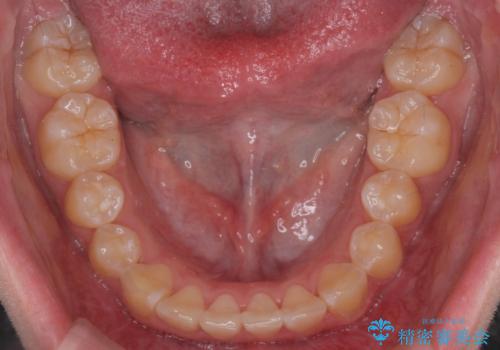

前歯のがたつき気になる。インビザラインモデレート

- 前歯のがたつきが気になるとの事で来院。

マウスピース矯正希望でしたのでインビザラインモデレートで治療を行いました。

がたつきが無くなり満足して頂けました。

矯正が終わった後は保定装置を使用しないと後戻りしてしまうのでしっかりと保定装置を使用する必要があります。